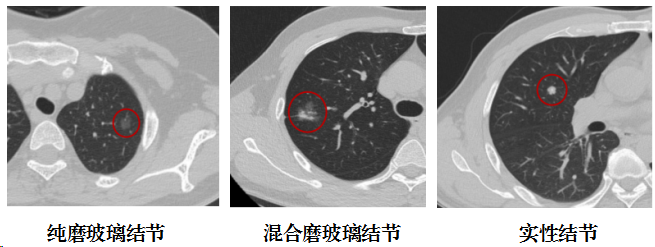

肺结节是指影像学表现为直径≤3cm的局灶性、类圆形、密度增高的实性或亚实性肺部阴影,可为孤立性或多发性。孤立性结节多无明显症状,多发性结节常表现为单一结节伴有一个或多个结节,一般认为>10个的弥散性结节多为恶性肿瘤转移或良性病变。局部病灶直径>3cm者称为肺肿块,恶性的可能性相对较大。